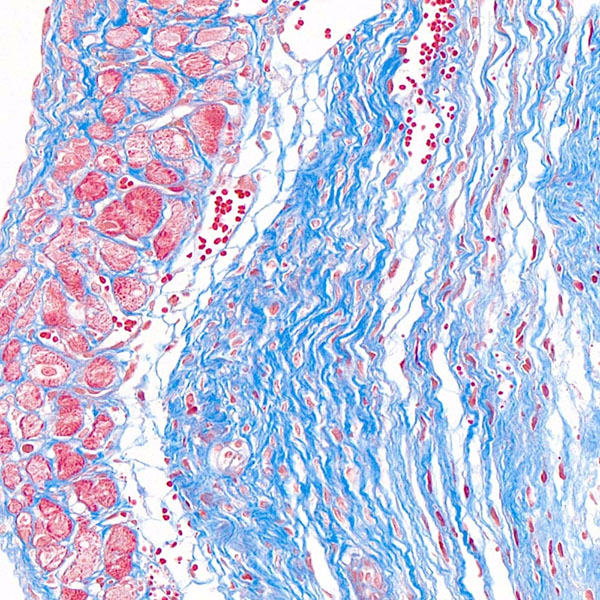

天狼猩红染色

Masson染色